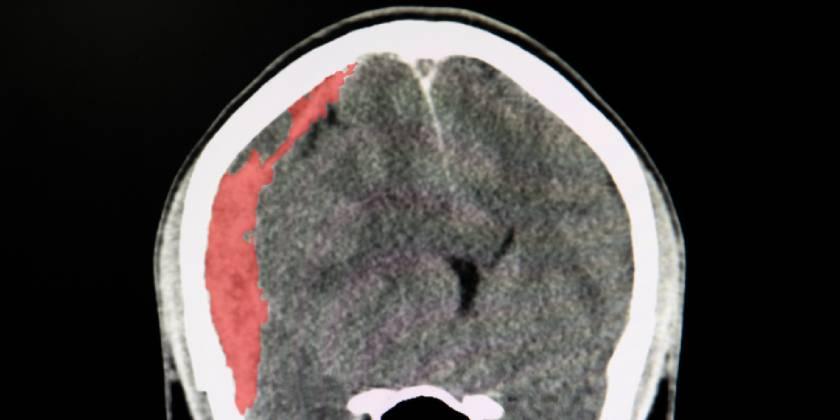

Eficacia y seguridad de la dexametasona en el hematoma subdural crónico

Un ensayo clínico mostró que el corticoide se asoció a peores resultados clínicos a los seis meses en comparación con placebo, pero con menor cantidad reoperaciones. New England Journal of Medicine, 16 de diciembre de 2020.